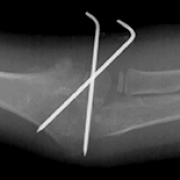

24 Jan 2024 : Clinical Research

Impact of COVID-19 Lockdown on Traumatic Bone Fracture Patterns and Hospital Outcomes in 1646 Elderly Patients: A Retrospective Study in Turkey

Ahmet Akif Durak

, Mehmet Ergin

, Selahattin Gürü

, Hakan Oğuztürk

, Gulhan Kurtoglu Celik

, Servan Gökhan

, Mehmet Ali Ceyhan

DOI: 10.12659/MSM.942916

Med Sci Monit 2024; 30:e942916

2,916 1,949 0

2916 1949 0